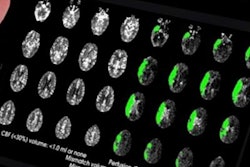

Cerebrovascular imaging software developer iSchemaView said that its Rapid neuroimaging software platform has now been installed at 520 stroke centers in 22 countries around the world. In addition, more than 55 other centers have committed to deploying the platform, according to the vendor.

The number of Rapid installations has increased by 48% since April, iSchemaView said. Rapid is also being used in six multicenter clinical trials around the world, adding 200 hospitals to the company's installed base.